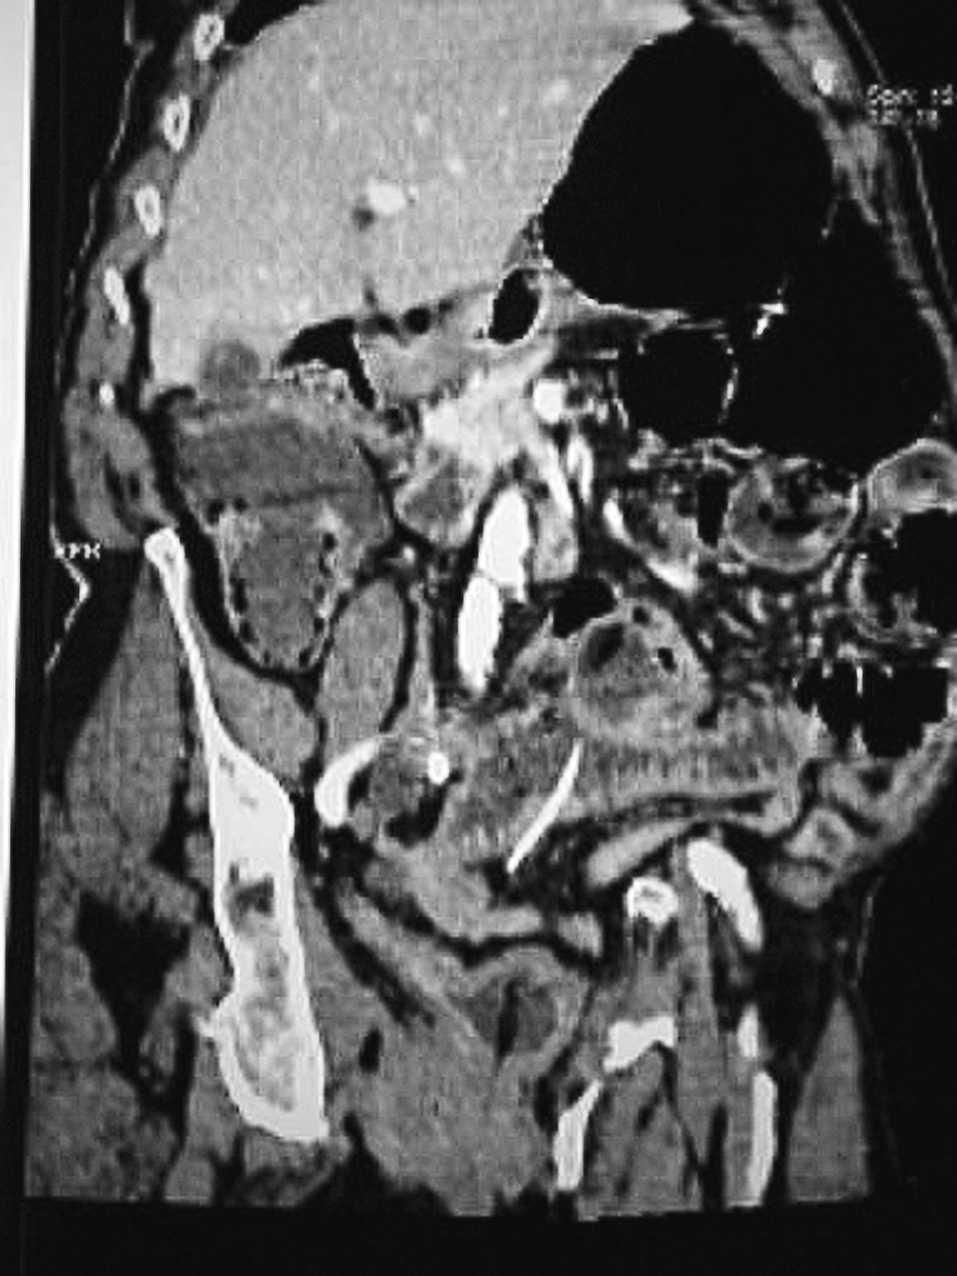

Mujer de 87 años, hipertensa, que consulta en urgencias por distensión abdominal y vómitos de 4 días de evolución. En la exploración física se aprecia un abdomen distendido y timpánico, doloroso a la palpación difusa, sin tumoraciones. La analítica mostraba 13.800 leucocitos/ml con neutrofilia. En la radiografía simple de abdomen se observaban asas de intestino delgado y colon dilatadas. Con la orientación diagnóstica de oclusión intestinal se realizó una tomografía computarizada (TC) abdominal con enema de gastrografín que mostró buen paso de contraste hasta el ángulo esplénico del colon. Ante la agravación del cuadro clínico se decidió realizar una intervención quirúrgica en la que se encontró una peritonitis localizada, secundaria a una doble perforación yeyunal por cuerpo extraño (fig. 1), por lo que se realizó una resección segmentaria de intestino delgado. Tras el hallazgo operatorio, se realizó una reconstrucción sagital de la TC que permitió la detección de ese cuerpo extraño (fig. 2).

Fig. 2.